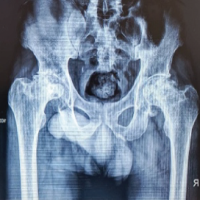

This was a prospective, observational study conducted in the Department of Orthopedics, Pt. J.N.M. Medical College and Dr. B.R.A.M. Hospital, Raipur (C.G.), after obtaining approval from the Institutional Ethical Committee. The study period extended from March 2023 to March 2025. All patients fulfilling the selection criteria and admitted during this period were included. Patients who underwent arthroscopic ACL reconstruction with simultaneous meniscus repair formed the study group. Data were collected using a structured and pre-validated pro forma. Each patient underwent detailed history taking, thorough clinical and radiographic examination, followed by surgical intervention. Loss to follow-up was considered as a potential source of bias. Inclusion criteria consisted of patients above 18 years of age with a traumatic ACL tear associated with medial, lateral, or combined meniscal injury, where the injury was <1-year-old. Exclusion criteria included ACL tears associated with fracture, collateral ligament or complex multi-ligament injuries, ipsilateral bony injuries, significant osteoarthritis, pathological degenerative ACL tears (such as due to mucoid degeneration), meniscal injuries not amenable to repair, and patients unwilling to give consent. Informed written consent was obtained from all participants in Hindi or English, using a patient information sheet and consent form.

Type of ACL tear

In our study, 10 out of 14 patients (71.4%) experienced a complete ACL tear, while the remaining 4 patients (28.6%) had a partial tear (Table 3).

Table 3: Type of ACL tear

Side of meniscus injury

In our study, the medial meniscus was injured in 10 out of 14 patients (71.4%), whereas the lateral meniscus was injured in 4 patients (28.6%) (Table 4).